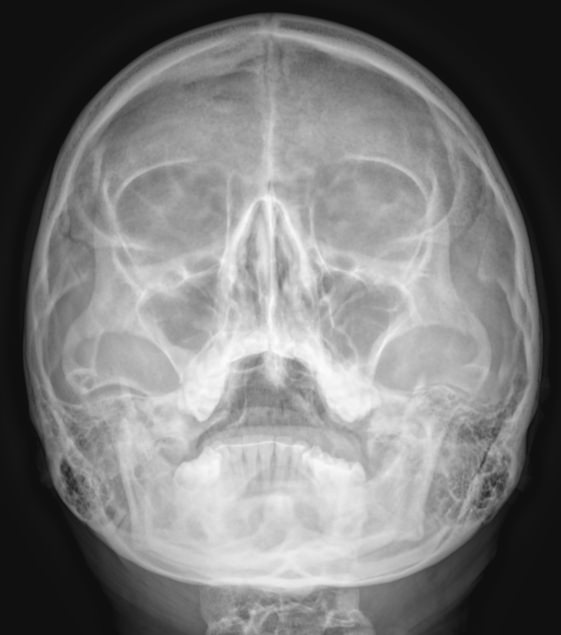

Придаточные или околоносовые пазухи носа ― это система воздухоносных полостей, располагающихся в костях черепа. Пазухи или синусы увлажняют и согревают вдыхаемый воздух, участвуют в формировании голоса, делают кости лица более легкими и смягчают силу удара при травме. К пазухам относятся:

• Гайморовы или верхнечелюстные ― расположены в верхней челюсти;

• Лобные ― в области лба над орбитами;

• Решетчатые ― позади носовых ходов  между орбитами;

• Клиновидные ― в глубине, за решетчатыми.

Что покажет рентген придаточных пазух носа

• Носовая перегородка ― прямая, искривленная, утолщенная;

• Носовые ходы ― свободны, сужены;

• Контур слизистой внутри пазух ―слизистая  обычная, утолщенная, есть рубцевания;

• Внутренние контуры ― четкие, расплывчатые;

• Наличие воздуха ― пневматизация сохранена, снижена;

• Жидкость ― в норме быть не должна, но если она есть, будет виден ее уровень;

• Новообразования;

• Инородные тела.

Правые и левые одноименные пазухи могут поражаться одновременно. Или одна быть здоровой, а другая иметь патологические изменения.